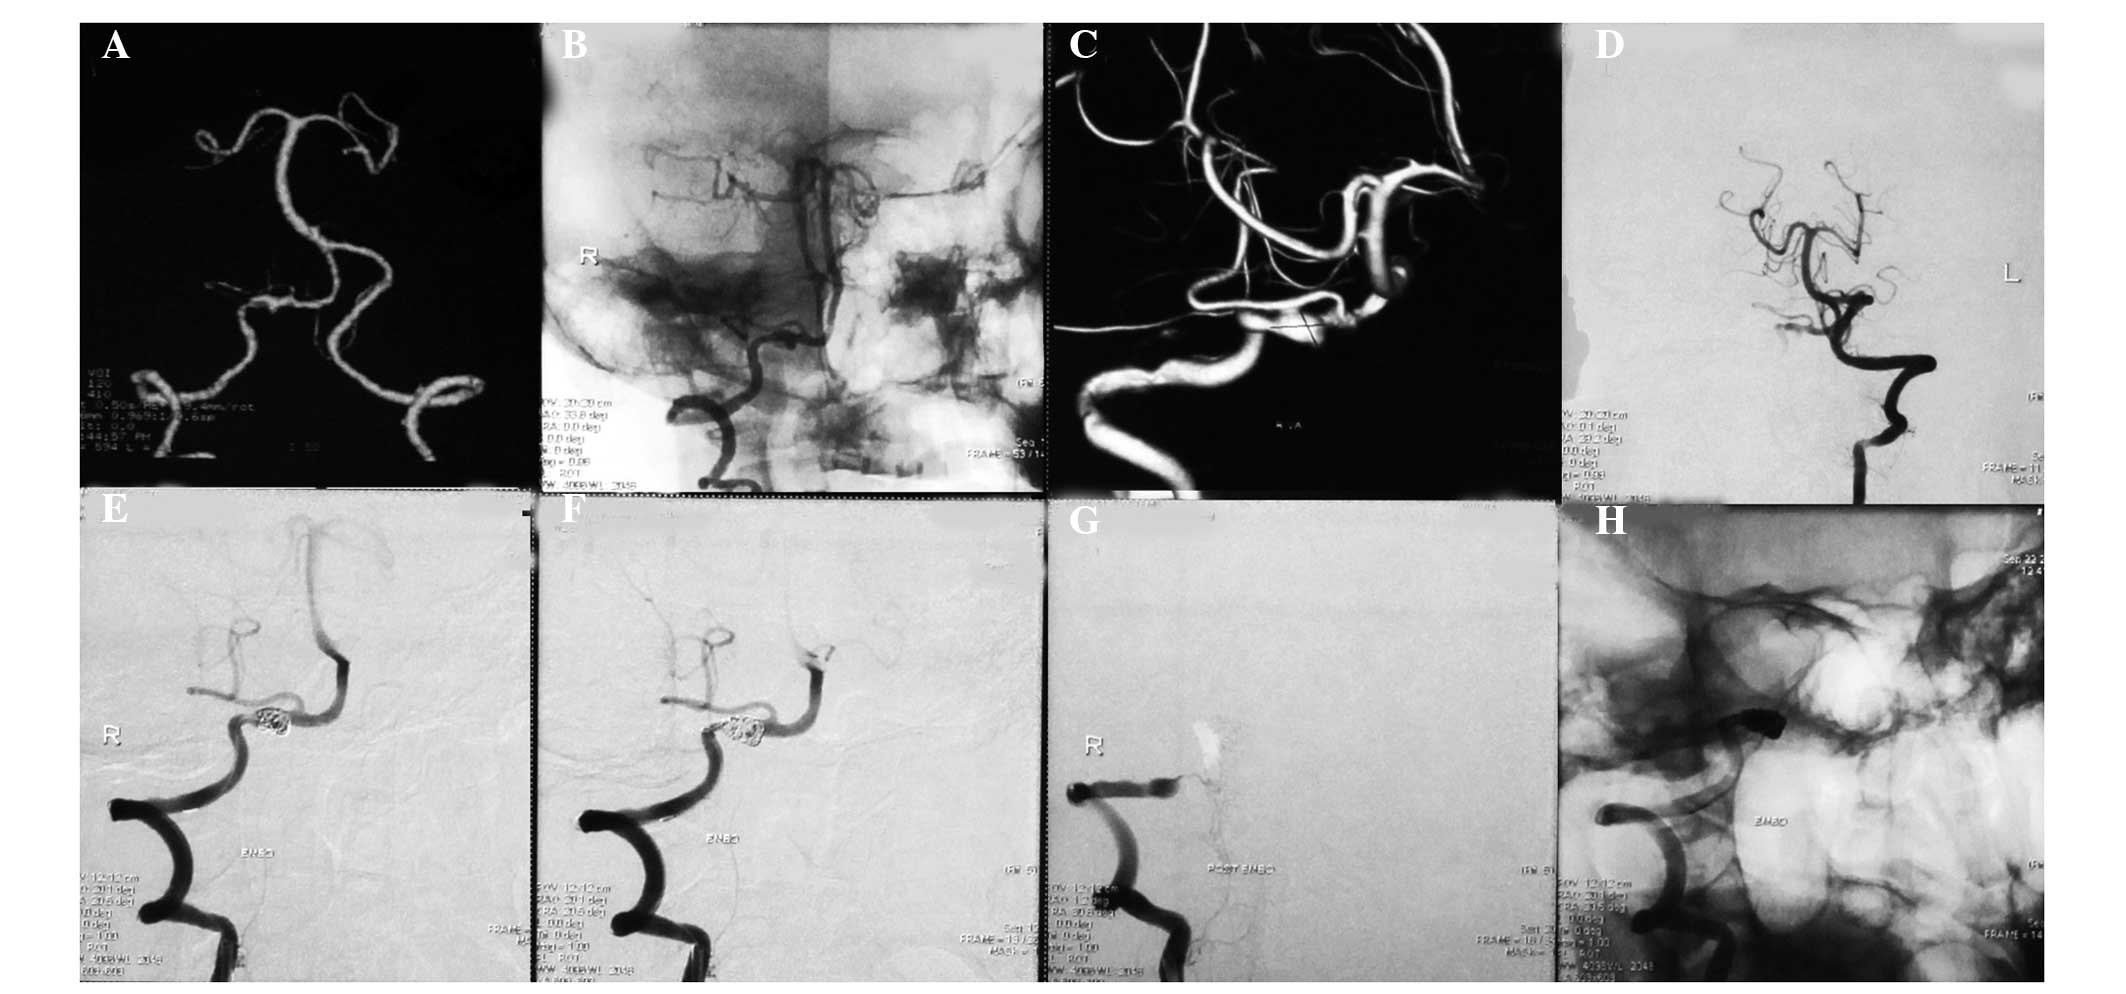

(A) Computed tomography angiography image showing the bilateral vertebral artery. (B) Negative and (C) 3D digital subtraction angiography (DSA) images showing a well-developed type IIIa dissecting aneurysm of the right vertebral artery located proximally to the posterior inferior cerebellar artery and the contralateral vertebral artery. The aneurysm was treated with coiling combined with right vertebral artery occlusion. (D) DSA image of the left vertebral artery. The post-treatment angiograms show (E) complete obliteration of the aneurysm and (F and G) occlusion of the distal part of the right vertebral artery. (H) Negative image of the right vertebral artery following treatment.

Among the 10 patients with type I aneurysms, four patients with type Ia received coiling with parent artery occlusion (Fig. 1), one patient with type Ia received stent-assisted coiling, three patients with type Ib received stent-assisted coiling (Fig. 2), one patient with type Ib received coiling only and one patient with type Ib was treated conservatively. Among the 13 patients with type II aneurysms, two patients with type IIa received coiling with parent artery occlusion (Fig. 3), five patients with type IIa received stent-assisted coiling (Fig. 4) and all six patients with type IIb received stent-assisted coiling. Among the eight patients with type III aneurysms, four patients with type IIIa received coiling with parent artery occlusion (Fig. 5), one patient with type IIIa received stent-assisted coiling (Fig. 6), two patients with type IIIb received stent-assisted coiling and one patient with type IIIb received coiling only.